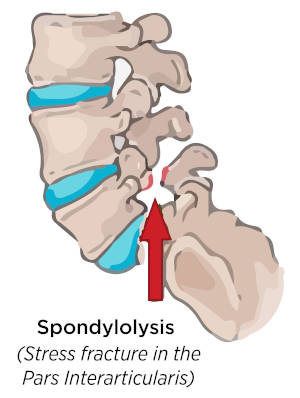

Όπως και σε επιφυσιόλυση (επαναλαμβανομενες κινήσεις σε υπερέκταση κυρίως στην ρυθμική, κολύμβηση, κωπηλασία) όπου έχουμε λύση του ισθμού του σπονδυλικού τόξου.

Εκτός της υπερκαταπόνησης προδιαθεσικοί παράγοντες για την εμφάνισή της είναι η έλλειψη vitD, και γενετικοί εμβιομηχανικοί παράγοντες, χωρίς όμως να υπάρχει σαφής αιτιολογία. Η γρήγορη διάγνωση σε πρώιμα στάδια, η απομόνωση εκλυτικών παραγόντων η αποφόρτιση και κινησιοθεραπευτικό πρόγραμμα ελαττώνουν σημαντικά το χρόνο αποχής από την άθληση. Σε προχωρημένα στάδια απαιτείται χειρουργική αποκατάσταση.